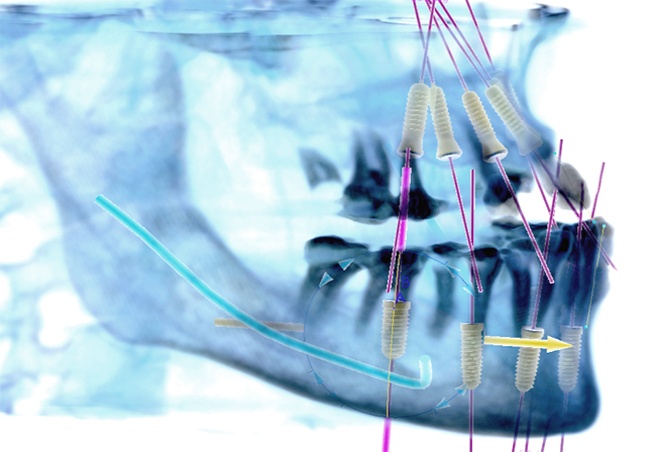

Computer-Guided Surgery

Computer-guided surgery, with the aid of modern and increasingly sophisticated software, enables the surgeon to plan the operation by means of a computer program, step by step, starting from a proper dental CT scan. It also allows very accurate transformation of this virtual surgery to a non-traumatic and micro-invasive real surgery.

After the 3-D CT scan of the dental area to be treated is completed, this scan will be imported into a highly technological software program that will elaborate two- and three-dimensional anatomical structures, enabling us to carry out a virtual computer simulation. We plan the implant placement and prosthetic structure precisely to a tenth of a millimeter. Other additional advantages of this method are the possibility of preventing surgical risk, the speed of this operation, and the rehabilitation period of the patient without the impact characteristics of traditional techniques.